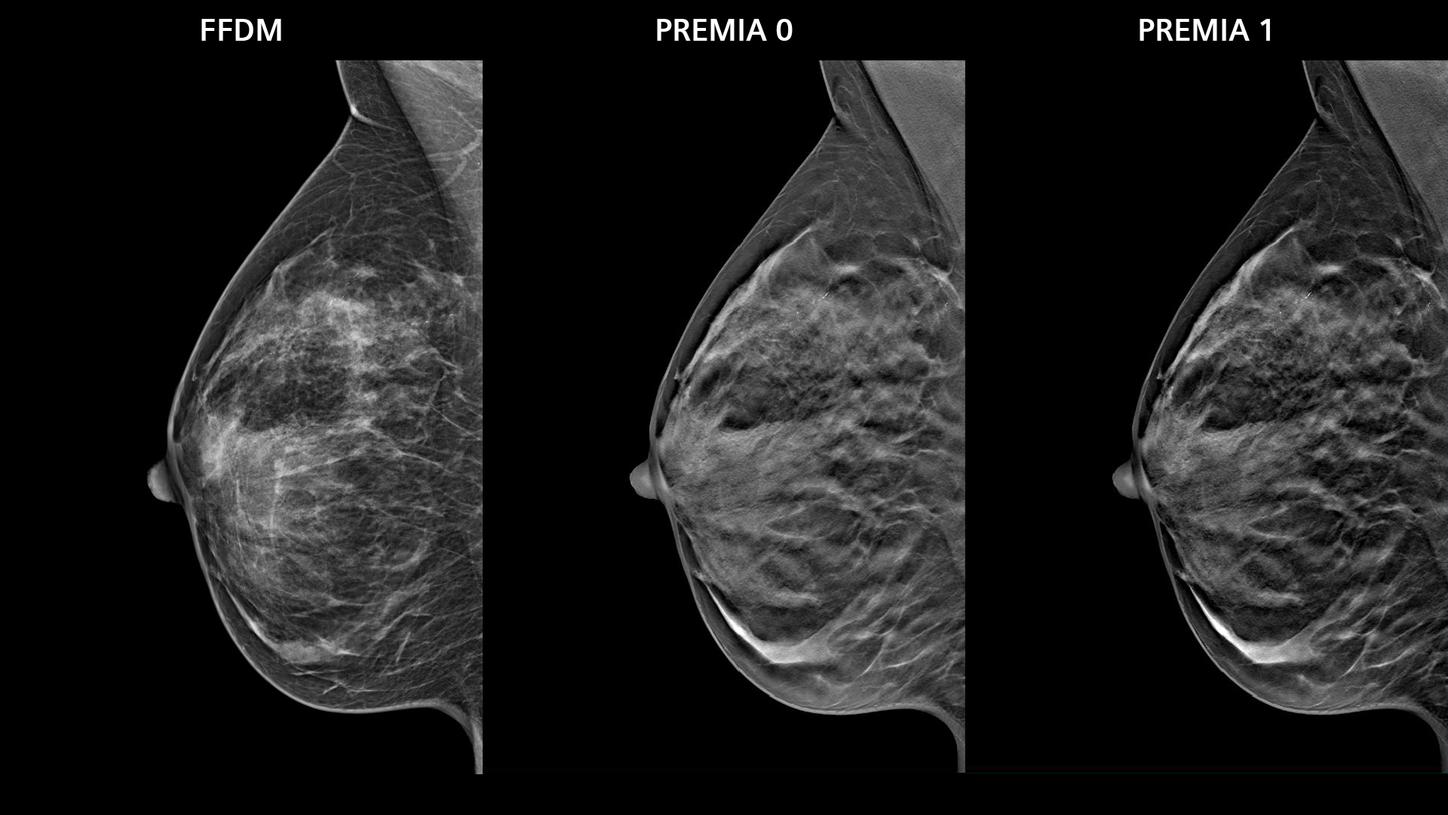

• PREMIA image reconstruction:

Improved image reconstruction framework

• Reduce artifacts and enhance visibility of calcifications and lesions

• Comfortable transition from 2D and narrow-angle systems, thanks to customizable image impressions

• Boost synthetic mammogram sharpness, thanks to AI-powered noise reduction

Image impression

5 different options for contrast and image sharpness for FFDM and synthesized 2D.